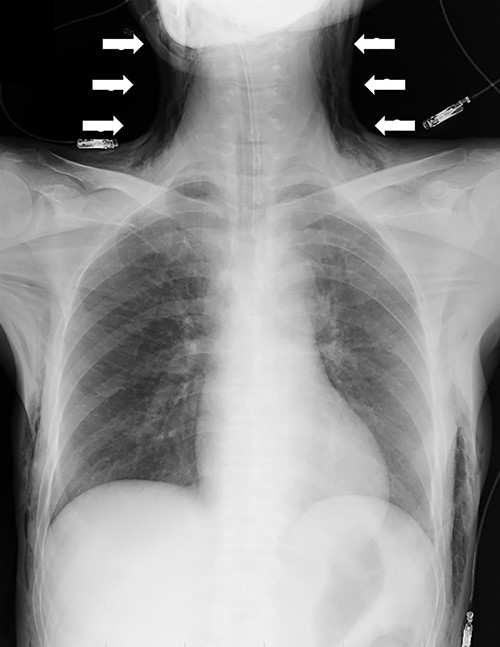

Although in Trendelenburg position, the patient was intubated and placed under general anesthesia. A uterine manipulator was fixed on the cervix to enable uterine mobilization. A 5-mm trocar was inserted through the umbilicus. The abdomen was insufflated with CO2 at a maintenance pressure of 12 mmHg. Two 5-mm trocars were placed on each side of the lower abdomen. A 12-mm trocar was then inserted in the middle of the lower abdomen. Intraoperatively, a large right ovarian cyst adherent to the uterus and retroperitoneum was identified in the pouch of Douglas (Fig. 1). Several endometriotic spots were observed in the pelvic cavity. Moreover, the pouch of Douglas was partly closed with the adhesions. These findings were consistent with the diagnosis of endometriosis Stage IV based on the revised American Society for Reproductive Medicine (r-ASRM) classification [2]. However, after 1 h, the patient presented with subcutaneous emphysema extending the anterior chest wall with an associated increase in end-tidal CO2 from 40 to 50 mmHg. Reducing the insufflation pressure from 12 to 8 mmHg and increasing the frequency of ventilation improved the patient’s condition. Peeling off those adhesions, the total laparoscopic hysterectomy and bilateral salpingo-oophorectomy were performed without complications. However, the peritoneum was massively disrupted such that the upper and lower peritoneum could not be sutured (Fig. 2). The total operation time was 3 h and 49 min. Pre-extubation chest radiography showed progression of the subcutaneous emphysema to the mandible in the absence of pneumothorax or pneumomediastinum (Fig. 3). This prompted close observation and continuation of mechanical ventilation. After 24 h, the subcutaneous emphysema of the neck was reduced and the patient was extubated. On the sixth postoperative day, the subcutaneous emphysema was completely resolved and she was discharged without any complications.

Chest radiography demonstrating the progression of the subcutaneous emphysema to the mandible (arrows).